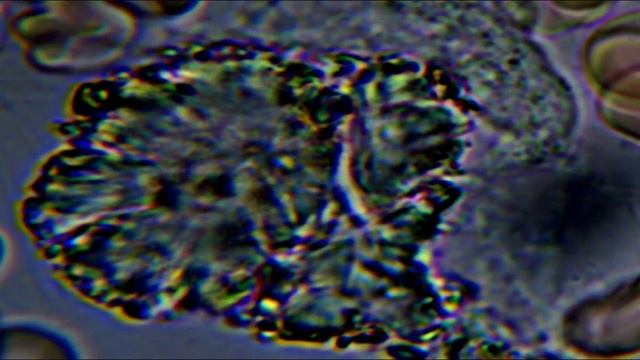

Видео Тест крови 2 Биология с яркостью Опубликовано 13.11.2024 в 00:00:00 Продолжительность: 00:03:00 3 . Видео , видео от 2024-11-13 загрузил на rutube Биология с яркостью...